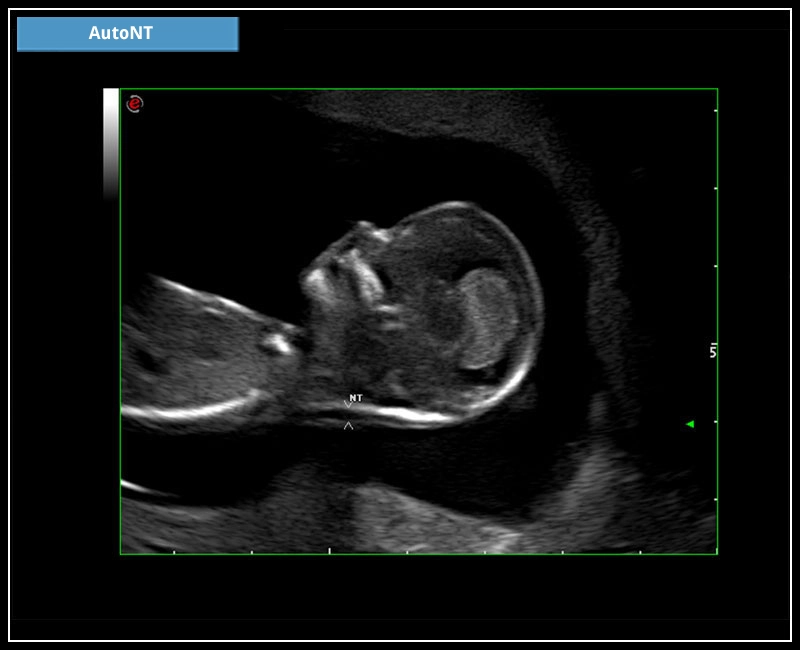

MyLab™9 Platform - HD Zoom on fetus profile with AutoNT measurement

MyLab™9 Platform - HD Zoom on fetus profile with AutoNT measurement

MyLab™X5 - AutoNT

MyLab™X5 - AutoNT

MyLab™X6 - AutoNT

MyLab™X6 - AutoNT

MyLab™X7 - AutoNT

MyLab™X7 - AutoNT